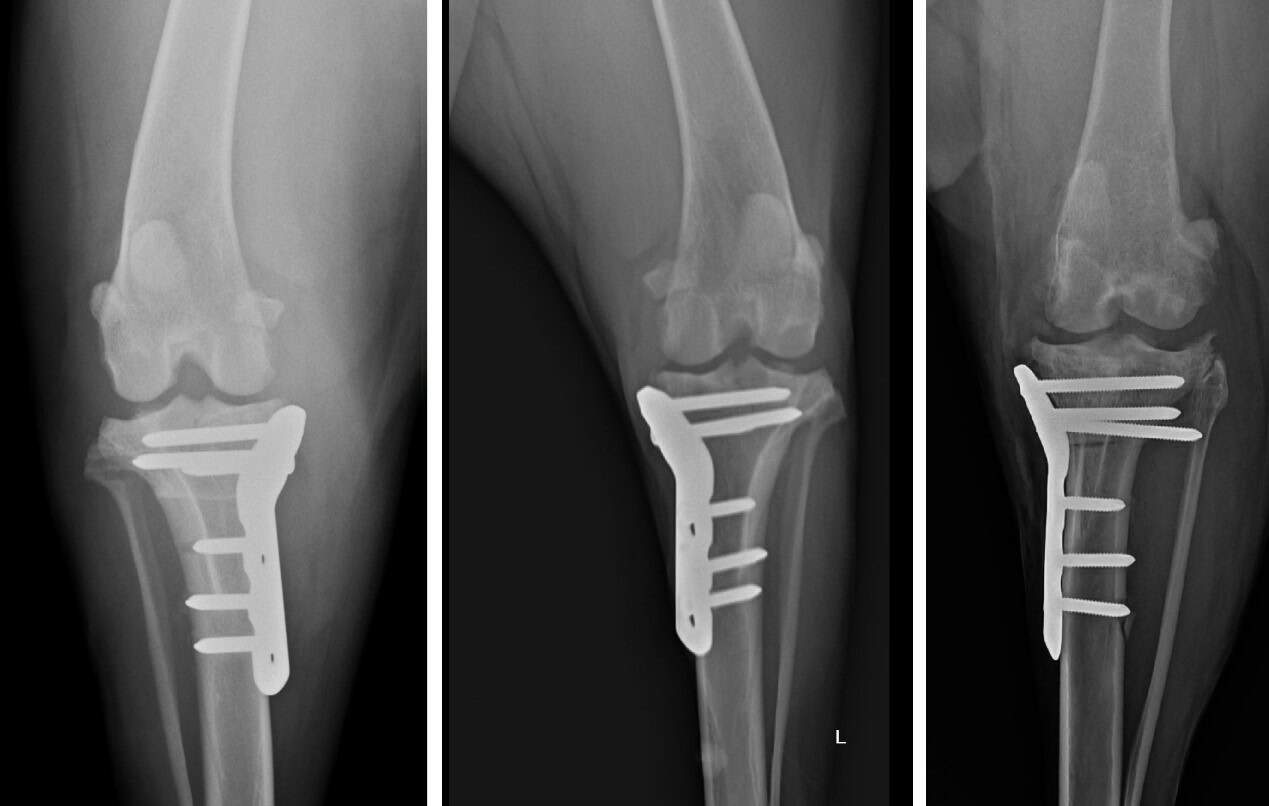

TPLO (Tibial Plateau Leveling Osteotomy) 是目前國際公認治療前十字韌帶斷裂的黃金標準手術。

它的原理非常巧妙: 既然韌帶斷了,我們不再執著於修補那條脆弱的韌帶,而是透過幾何力學的改變,將脛骨切開並旋轉角度,改變膝關節受力的平臺。術後,狗狗的膝蓋不再需要依靠前十字韌帶就能在行走時保持穩定。